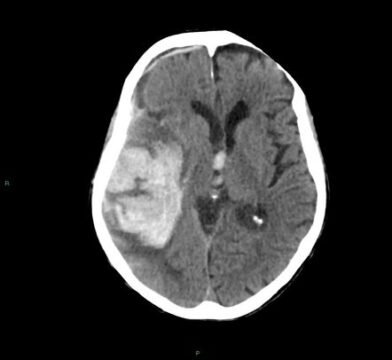

Imagem 3

Imagem 3: TC de crânio sem contraste mostrando hemorragia intracerebral lobar extensa (provavelmente fronto-parietal), hiperdensa, com efeito de massa local e discreta compressão do ventrículo lateral adjacente.

Não há predomínio de sangramento profundo (tálamo/núcleos da base).Padrão compatível com hemorragia lobar espontânea, sugestiva de angiopatia amiloide cerebral no idoso, no contexto clínico apropriado.

Fonte: https://radiopaedia.org/cases/cerebral-amyloid-angiopathy-associated-lobar-intracerebral-haemorrhage-19?case_id=cerebral-amyloid-angiopathy-associated-lobar-intracerebral-haemorrhage-19&lang=gb